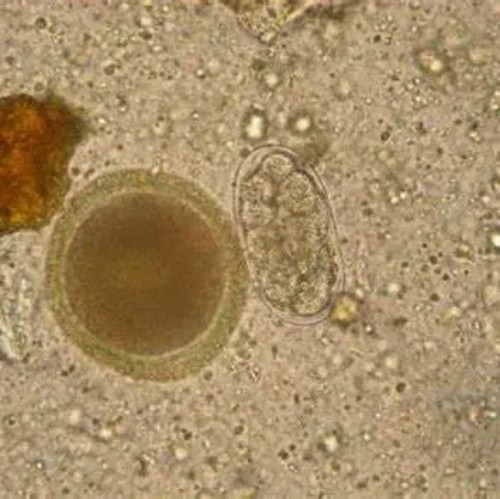

04【诊断标准】 根据临床症状和粪便检查时发现虫卵即可确诊。